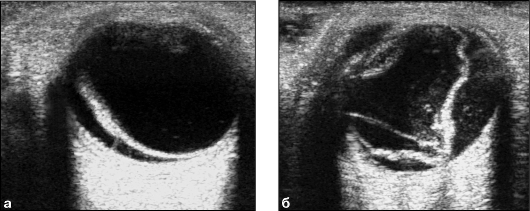

Рис. 10. Эхограммы глазного яблока: а) свежее

кровоизлияние в полости стекловидного тела, б) формирование

соединительнотканных тяжей, фиброз стекловидного тела

УЗИ: свежие кровоизлияния отображаются при

эхографии в виде небольших гиперэхогенных включений. Иногда удается выявить их

свободное перемещение внутри глаза при смещениях глазных яблок, в более поздние

сроки гемофтальма формируются плотные внутриглазные тяжи и образуются шварты